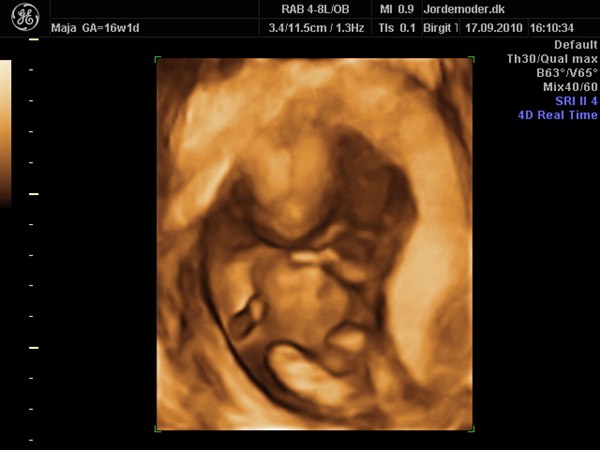

Vi var i fredags til scanning hvor jeg var 16+1 og det var en super fed oplevelse, selvom den lille var genert

vi ønsker ikke at vide kønnet, så er jo dejligt vi alligevel kunne få lov at opleve 3D

Vi har derudover snakket om at få lavet 3D når jeg er 27+1, nogle der har fået lavet 3D omkring der, og hvad har oplevelsen været, vi vil jo gerne vælge det bedste tidspunkt, for at få så meget oplevelse som muligt ud af det, også da vi har planer om at den kommende mormor og farmor skal med

Vedhæftede fotos (klik for at se i fuld størrelse)